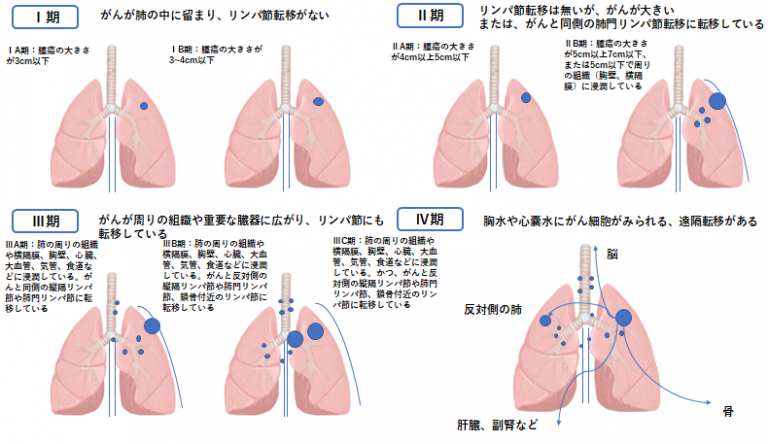

がんの病期は、原発(元の)腫瘍の大きさと、それが体の局所的部分または遠隔部分に転移しているかどうかに関する情報を提供します。

NSCLCは 0 から 4 に分類されます。数値が低い場合は、がんがそれほど遠くまで広がっていないことを意味します。

ステージ 1 の肺がんでは、原発 (元の) 腫瘍は 4 センチメートル (cm) 以下です。さらに、がん細胞はリンパ節や体の離れた部分(他の臓器など)には広がっていません。

ステージ 1 の肺がんは、以下に従って 4 つのサブステージに分類されます。

- ステージ1A1。医師がステージ 1A1 の肺がんを診断するシナリオは 2 つあります。

- 腫瘍は1cm以下です。

- この腫瘍は腺癌であり、粘液を作る肺細胞に由来します。 3cm以下です。肺組織の深部に転移した腺癌は 0.5 cm 未満です。

- ステージ1A2。腫瘍の大きさは1~2cmです。

- ステージ1A3。腫瘍の大きさは2~3cmです。

- ステージ1B。以下の記述のうち少なくとも 1 つが当てはまる場合、医師はステージ 1B の肺がんと診断します。

- 腫瘍の大きさは3~4cmです。

- 腫瘍は 2 本の主気管支 (気道) の 1 つに成長していますが、気管分岐部 (気管支を分割する軟骨) から少なくとも 2 cm 離れています。腫瘍の大きさは4cm以下です。

- 腫瘍は肺を覆う膜である内臓胸膜まで増殖しました。腫瘍の大きさは4cm以下です。

- 腫瘍は気道を部分的に閉塞していますが、大きさは 4 cm 以下です。